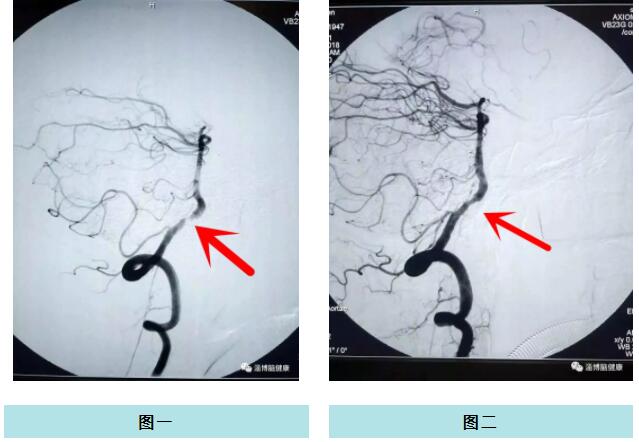

圖一為術(shù)前造影影像;圖二為術(shù)后造影影像。

70歲的高大爺,有高血壓、冠心病,經(jīng)常出現(xiàn)頭暈眼花等癥狀,有時(shí)候睡一覺(jué)就好了,也就沒(méi)怎么留意。半年前,出現(xiàn)反復(fù)頭暈、復(fù)視的癥狀,家人才意識(shí)到病情的嚴(yán)重性,立即同高大爺?shù)奖贝筢t(yī)療淄博醫(yī)院就診。神經(jīng)內(nèi)科主任王慶德,為患者進(jìn)行詳細(xì)的查體。為了逐一排除其他各種病因,進(jìn)一步明確診斷,為患者實(shí)施腦血管造影檢查,造影顯示患者椎動(dòng)脈狹窄,狹窄率達(dá)到了百分之九十,患者隨時(shí)有生命危險(xiǎn)。

神經(jīng)內(nèi)科副主任鐘濤與介入中心主任劉綿春將患者情況與家屬充分溝通并征得患者及家屬同意后,決定為患者實(shí)施“椎動(dòng)脈支架置入術(shù)”。該手術(shù)存在很大風(fēng)險(xiǎn),如果術(shù)中在放置支架治療時(shí)意外發(fā)生破裂出血,后果將不堪設(shè)想。鐘主任和劉主任對(duì)手術(shù)可能出現(xiàn)的并發(fā)癥也做了充分考慮和準(zhǔn)備,手術(shù)中采用多種裝置輔助輸送固定支架系統(tǒng),在狹窄段準(zhǔn)確釋放支架,將狹窄的血管管腔緩緩撐起,隨后造影顯示血管開(kāi)通,狹窄消失。術(shù)后病人恢復(fù)好,頭暈、復(fù)視緩解,患者及家屬非常滿意,現(xiàn)已康復(fù)出院。